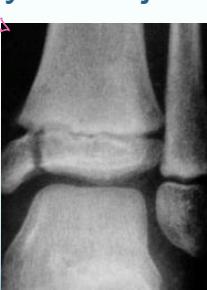

Physeal (Growth Plate) Injuries

- Epiphyseal injuries ⇒ Growth Arrest

- Physeal injuries

phyuseal injuries